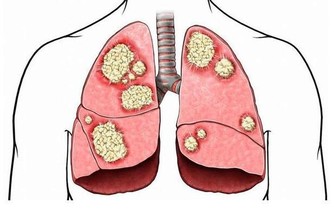

慢性鼻竇炎患者除了有上述症狀外,還會伴有咳嗽、支氣管炎和哮喘。